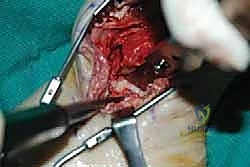

However, this talar body was completely avascular. Note the unhealthy appearance of the talar body ( TECH FIG 9A ).

The talar body is extracted from the joint, in this case using a chisel. Note the fracture in the medial aspect of the talus that was revealed when the avascular lateral portion of talus is removed ( TECH FIG 9B,C ).

TECH FIG 9 • A. Avascular necrosis of the talar body. Note the unhealthy bone that is easily excavated from the inferolateral aspect of the talar body. B, C. Removal of the avascular talar body. B. Use of a chisel. C. Note the fatigue fracture in the medial talar dome that is visible with removal of the unhealthy lateral aspect of the talus.